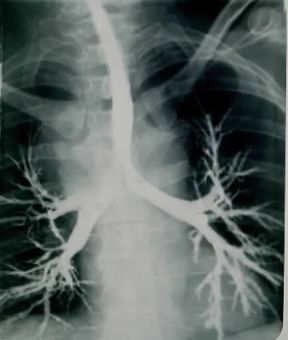

Broncografia di albero bronchiale alterato da bronchiettasia (le diramazioni bronchiali intrapolmonari appaiono dilatate).

sf. [bronco (anatomia)+-grafia]. Metodo di indagine radiografica che permette di ottenere immagini molto precise dell' albero bronchiale (broncogramma) mediante l'introduzione in esso di un mezzo di contrasto liquido radiopaco . A tale proposito si usano sondini molto sottili che vengono fatti pervenire nei bronchi per via nasale e sotto anestesia locale. Una volta iniettato il mezzo di contrasto, le radiografie mostrano chiaramente l'anatomia e la fisiologia (modificazioni del calibro con l'attività respiratoria o sotto i colpi di tosse) delle vie bronchiali. Le principali indicazioni della broncografia sono l'accertamento dell'eventuale esistenza di malformazioni congenite dei bronchi e la diagnosi di bronchiettasie. È inoltre possibile precisare l'estensione e la gravità della bronchite cronica.